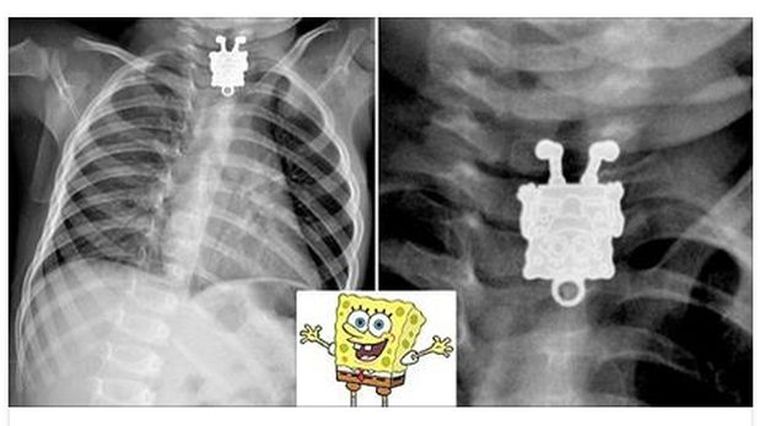

Un bebe se tragó un collar de Bob Esponja

En Facebook circula la imagen de unas placas realizadas a una bebe de 16 meses que se habría tragado un collar en forma de Bob Esponja de su hermana.

A un hospital de Yeda, Arabia Saudita, llegó una bebe que tenía signos de haberse tragado algo que le impedía respirar con normalidad. Los médicos tomaron placas a la menor y descubrieron que lo que había ingerido era un collar de forma del conocido personaje de dibujos animados, Bob Esponja. En la imagen de Facebook se puede distinguir claramente al personaje animado.

El doctor Ageely informó que el collar estaba atorado en el esófago de la pequeña. El colgante fue retirado de la garganta de la niña y fue dada de alta para recuperarse en casa, según informó el diario "Daily Mail" en su cuenta de Facebook.

Las imágenes compartidas en Facebook fueron puestas en un foro de radiólogos y de estudiantes de medicina en donde se discuten casos raros como este.